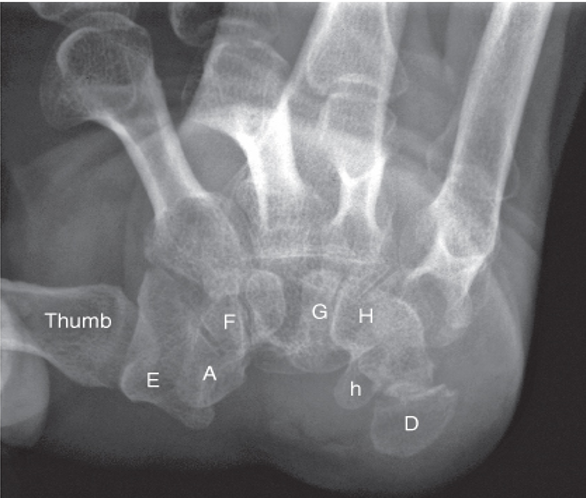

Q

What type of synovial joint is this

A

Plane (gliding)

Carpals shown